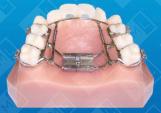

Arch development is a collective term that describes the purpose of a variety of appliances. Used to gain both arch width and arch length, these appliances range from the simple Schwarz appliance (with lap spring) to the high-speed, rapid palatal expanders. They may utilize orthodontic movement, orthopedic movement or a combination of both -- and may be either fixed or removable. With proper design, expansion appliances may be used to move teeth on either side of the arch unilaterally or bilaterally. They may be used to relieve crowding in the posterior segments, develop underdeveloped pre-maxillas, reposition retroclined anteriors, and relieve anterior crowding.

There are many indications for arch development. In children, the overwhelming majority of lateral expansion appliances are used to treat crossbites, crowded anteriors with an excessive overjet, or a combination of these conditions. In adults, arch development appliances are mainly used to correct crowding in the anterior region, upright lingually tipped posterior segments back over the basal bone, distalize mesially inclined molars, correct retroclined anteriors, and, in conjunction with straight wire therapy, round out narrow arches and align the occlusal planes. Arch development is also important for patients who need therapy to correct a skeletal problem.

- Combination Fixed Appliances for AP/Lateral Development